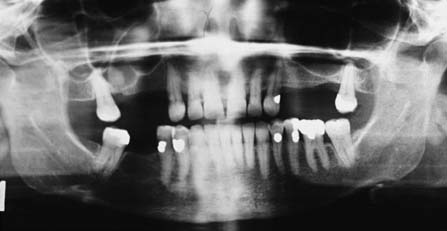

Panoramic films (Fig. 1-24) provide useful information about the presence or absence of teeth. They are especially helpful in assessing third molars and impactions, evaluating the bone before implant placement (see Chapter 13), and screening edentulous arches for buried root tips. However, they do not provide a sufficiently detailed view for assessing bone support, root structure, caries, or periapical disease.

Fig. 1-24 A panoramic film cannot be substituted for a full-mouth series because the image is distorted. Nevertheless, it is very useful for assessing unerupted teeth, screening edentulous areas for buried root tips, and evaluating the bone before implant placement.